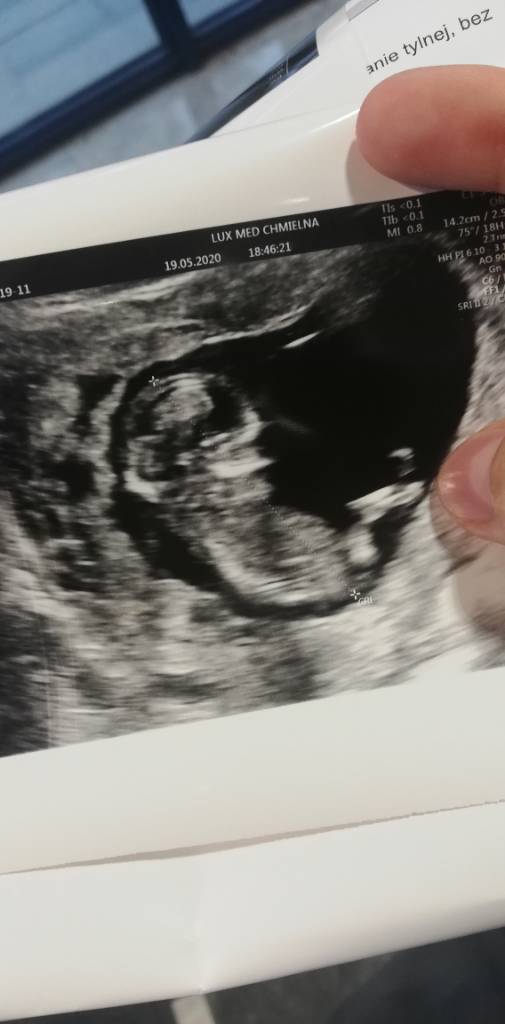

Nasz bobek [emoji3589]@monika1708 super wieści [emoji3590] masz jakieś zdjęcia?![]()

29. 11@monika1708 piękny Dzidziulek [emoji7][emoji7][emoji7] cieszę się, że wszystko w porządku u Was. Na kiedy masz termin? [emoji8]

Cudo [emoji7][emoji7][emoji7]Nasz bobek [emoji3589]Zobacz załącznik 1122090